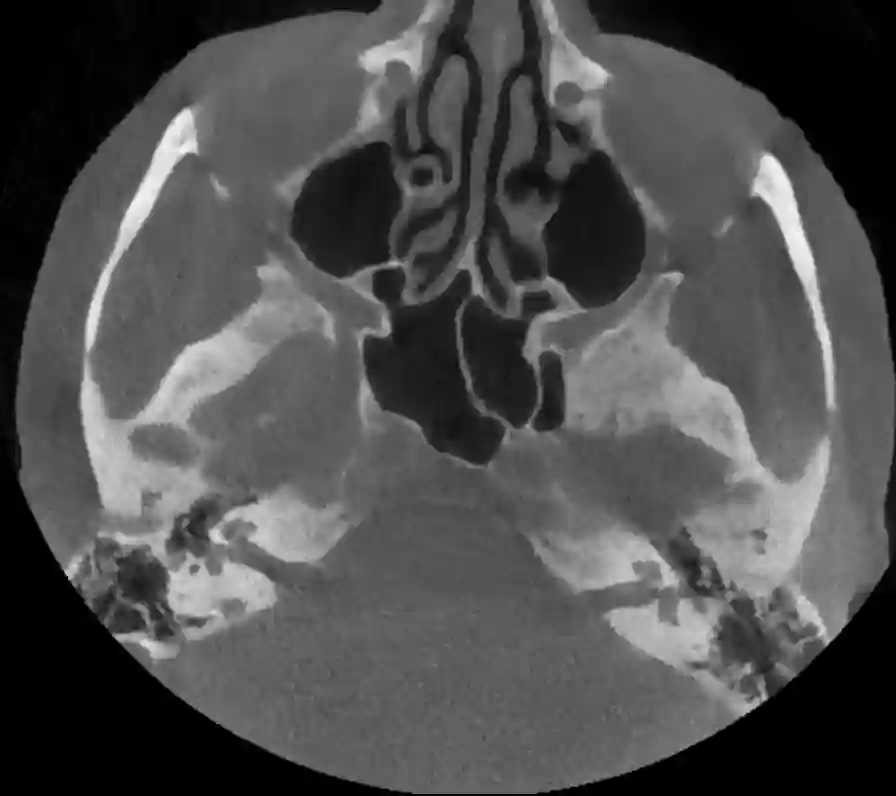

Axiales CT Bild des Felsenbeins

Axiales Schnittbild durch den Schädel auf Höhe des Felsenbeins.